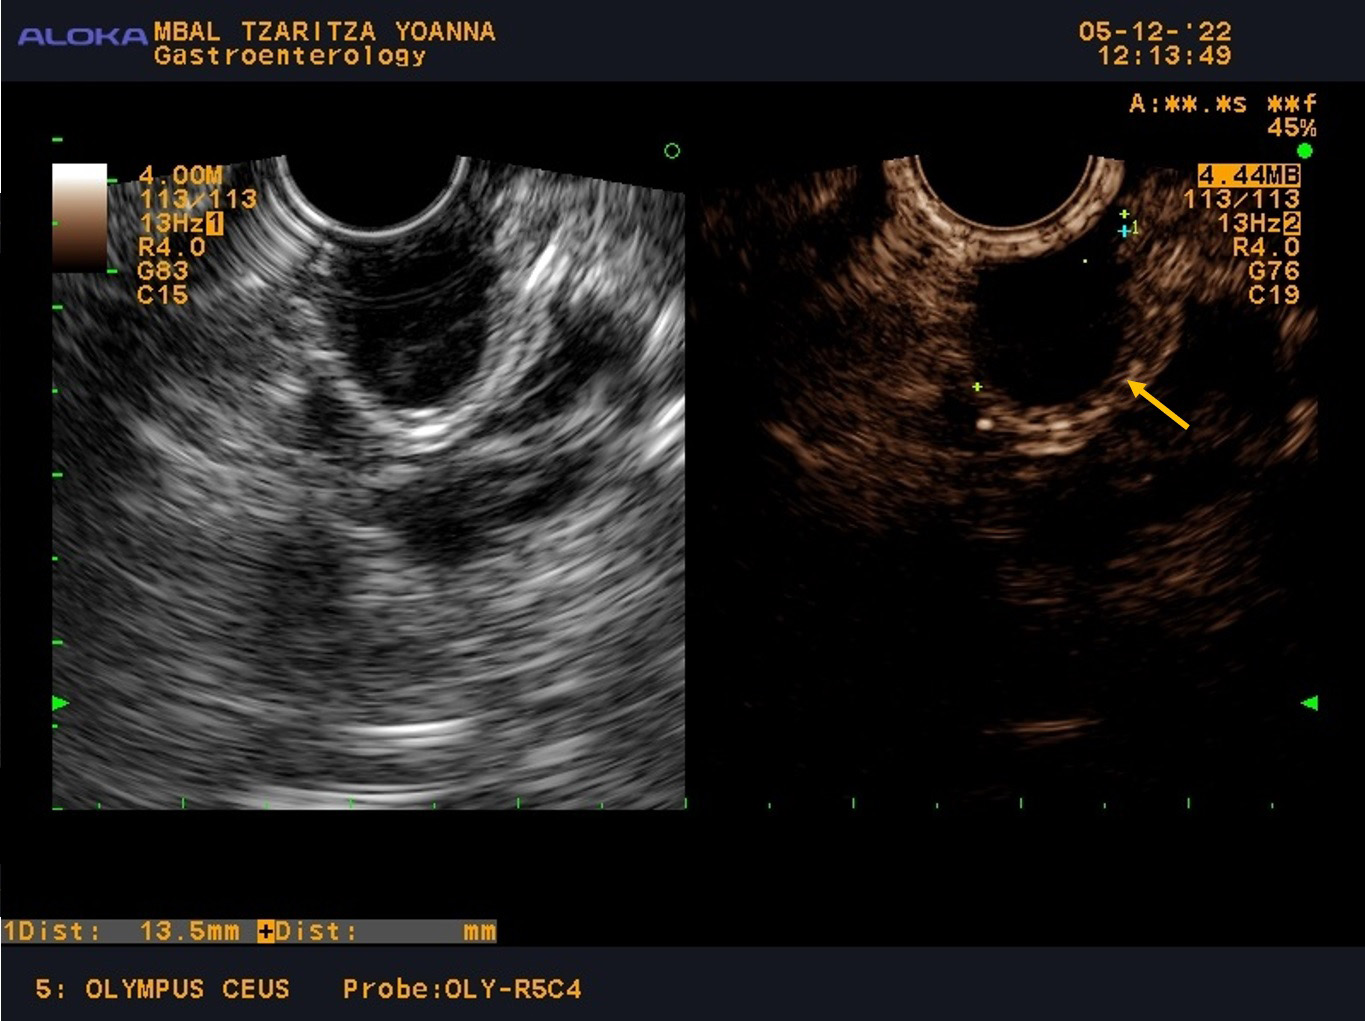

Due to the small size of the cyst and the absence of symptoms, the patient was scheduled for follow-up with EUS examinations every six months during the first year, with the interval subsequently extended to one year. Over the two years of follow-up (Fig. 3), there was no change in size (the cyst remains 13.5 mm) or any concerning features of the cyst, and the patient is slated for her next EUS examination after one year.

Fig. 3.

Control EUS examination during follow up.